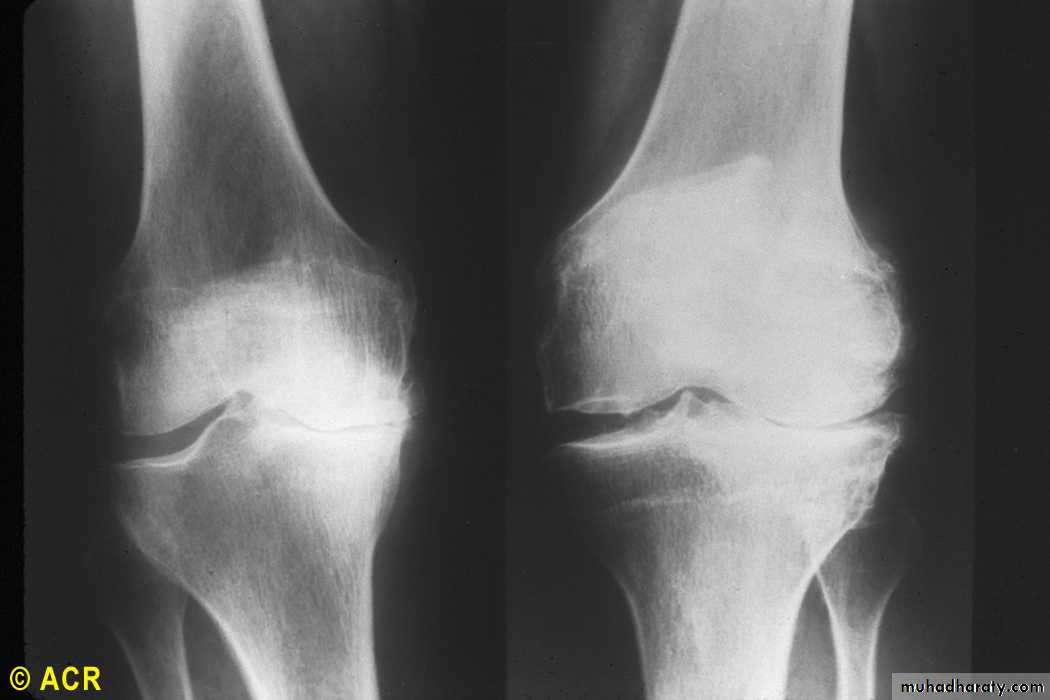

Osteoarthritis: knees, medial (XR1) and lateral (XR2)

cartilage degeneration Medial loss is the usual in

mobility /loading related O.A. knee